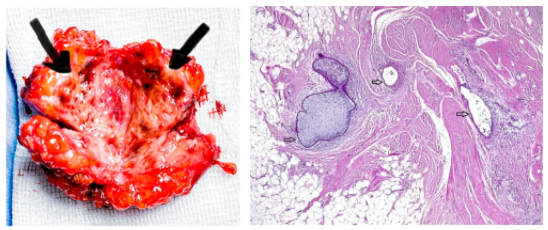

经腹超声显示一个不均匀、低回声的实性肿块,位于靠近剖腹产疤痕的皮下脂肪内,边缘不清。肿块内有散在回声,无多普勒信号。肿块显示出典型的特征(图3),组织学检查证实了诊断(图4)。

图3. 纤维组织内有许多带有巧克力状液体的囊肿(黑色箭头)

图4. 肿块的组织学表现为罕见的子宫内膜腺体和间质(箭头所示)嵌在结膜和脂肪组织内